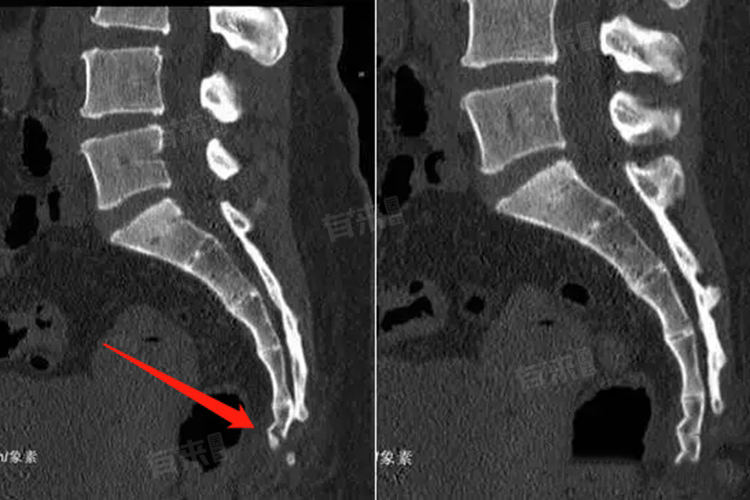

骶椎骨骨折的恢复时间受骨折程度、患者年龄、治疗方法和康复锻炼等因素影响,通常在4周到6个月甚至更长时间,患者应遵循医生的指导,积极配合治疗和康复,以促进骨折的愈合和身体的恢复。

- 骨折程度较重:若骨折有明显的移位,甚至伴有神经损伤,恢复时间会显著延长。患者可能会出现下肢麻木、无力、大小便失禁等症状,可能需要6-8周的卧床休养,然后佩戴支具逐渐下地活动,完全恢复可能需要3-6个月甚至更长时间。

- 保守治疗主要是卧床休息、佩戴支具等。采取保守治疗且骨折较轻的患者,恢复时间通常在8-12周。如果骨折严重,需要手术治疗,术后可能需要12-16周的康复期,才能逐渐恢复正常活动。